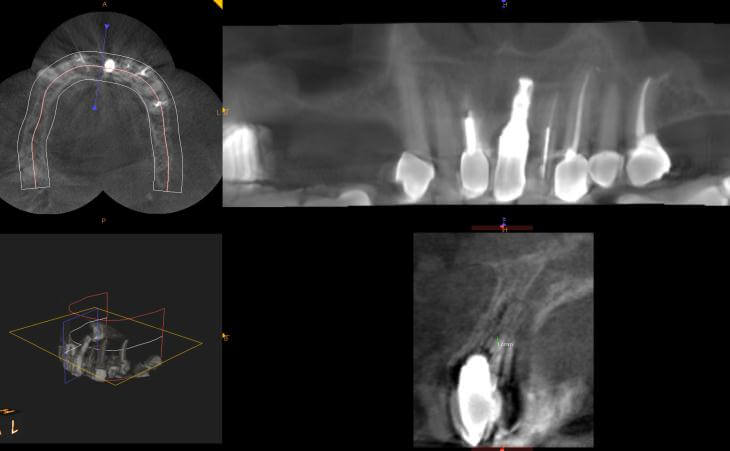

The patient had a decayed molar #14. It was removed and an immediate implant was placed in conjunction with an Internal Sinus lift procedure.

Patient had upper right molar extracted. CT scan revealed insufficient bone volume to place implant as is. Pt underwent INTERNAL SINUS LIFT procedure at the same time as Implant placement. This allowed bone grafting and implant placement to be performed together. State of the Art Surgery

Patient lost upper right molar due to decay. Had insufficient bone for implant placement without a bone graft. Underwent Internal Sinus lIft procedure with Immediate Implant Placement